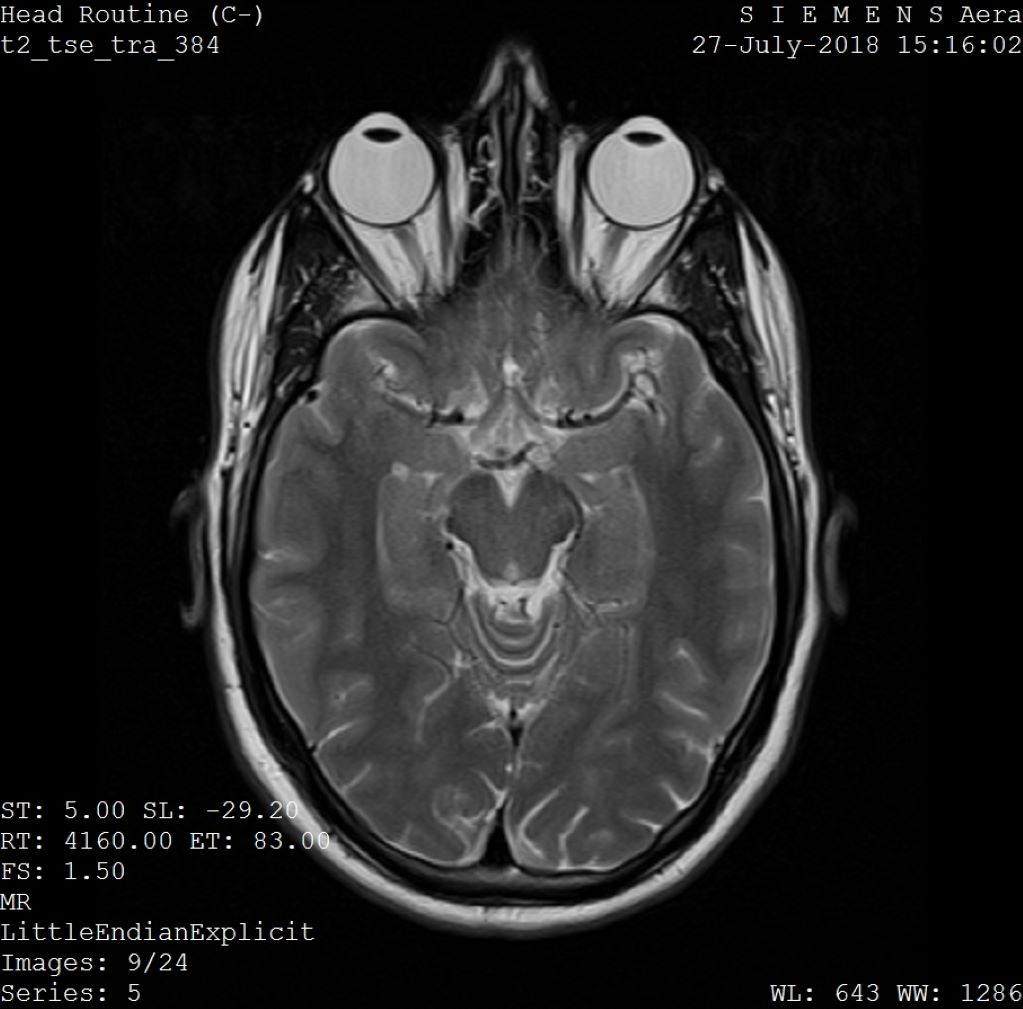

Ερευνητές του ΜΙΤ ανέπτυξαν ένα μοντέλο βαθιάς μάθησης που μπορεί να διορθώσει τα τεχνουργήματα κίνησης σε μαγνητικές τομογραφίες εγκεφάλου, οι οποίες είναι ιδιαίτερα ευαίσθητες στην κίνηση. Η μέθοδος δημιουργεί εικόνες χωρίς κίνηση χωρίς να αλλάζει η διαδικασία σάρωσης, ωφελώντας τα αποτελέσματα των ασθενών και μειώνοντας ενδεχομένως τις δαπάνες των νοσοκομείων. Η μελλοντική εργασία μπορεί να διερευνήσει τη διόρθωση της κίνησης σε άλλα μέρη του σώματος.

- Το μοντέλο κατασκευάζει υπολογιστικά μια εικόνα χωρίς κίνηση από δεδομένα που έχουν υποστεί αλλοίωση από την κίνηση, χωρίς να αλλάζει τίποτα στη διαδικασία σάρωσης.

- Η κίνηση στη μαγνητική τομογραφία οδηγεί συχνά σε τεχνουργήματα που μπορούν να αλλοιώσουν ολόκληρη την εικόνα, θέτοντας τους ασθενείς σε κίνδυνο λανθασμένης διάγνωσης ή ακατάλληλης θεραπείας.

- Το μοντέλο διασφαλίζει τη συνέπεια μεταξύ της εξόδου της εικόνας και των πραγματικών μετρήσεων αυτού που απεικονίζεται, αποφεύγοντας τις "ψευδαισθήσεις" που θα μπορούσαν να επιδεινώσουν τα αποτελέσματα.

Σε σύγκριση με άλλες μεθόδους απεικόνισης, όπως οι ακτίνες Χ ή οι αξονικές τομογραφίες, οι μαγνητικές τομογραφίες παρέχουν υψηλής ποιότητας αντίθεση μαλακών ιστών. Δυστυχώς, η μαγνητική τομογραφία είναι ιδιαίτερα ευαίσθητη στην κίνηση, με αποτέλεσμα ακόμη και οι μικρότερες κινήσεις να προκαλούν τεχνουργήματα εικόνας. Αυτά τα τεχνουργήματα θέτουν τους ασθενείς σε κίνδυνο λανθασμένης διάγνωσης ή ακατάλληλης θεραπείας, όταν κρίσιμες λεπτομέρειες αποκρύπτονται από τον ιατρό. Αλλά οι ερευνητές του ΜΙΤ μπορεί να έχουν αναπτύξει ένα μοντέλο βαθιάς μάθησης ικανό για τη διόρθωση της κίνησης στη μαγνητική τομογραφία εγκεφάλου.

Οι συνεδρίες μαγνητικής τομογραφίας μπορούν να διαρκέσουν από λίγα λεπτά έως μία ώρα, ανάλογα με το είδος των εικόνων που απαιτούνται. Ακόμη και κατά τη διάρκεια των πιο σύντομων σαρώσεων, μικρές κινήσεις μπορεί να έχουν δραματικές επιπτώσεις στην εικόνα που προκύπτει. Σε αντίθεση με την απεικόνιση με κάμερα, όπου η κίνηση εκδηλώνεται συνήθως ως τοπική θολούρα, η κίνηση στη μαγνητική τομογραφία συχνά οδηγεί σε τεχνουργήματα που μπορούν να αλλοιώσουν ολόκληρη την εικόνα. Οι ασθενείς μπορεί να αναισθητοποιηθούν ή να τους ζητηθεί να περιορίσουν τη βαθιά αναπνοή, προκειμένου να ελαχιστοποιηθεί η κίνηση. Ωστόσο, αυτά τα μέτρα συχνά δεν μπορούν να ληφθούν σε πληθυσμούς ιδιαίτερα ευαίσθητους στην κίνηση, συμπεριλαμβανομένων των παιδιών και των ασθενών με ψυχιατρικές

Η εργασία, με τίτλο "Data Consistent Deep Rigid MRI Motion Correction", βραβεύτηκε πρόσφατα ως η καλύτερη προφορική παρουσίαση στο συνέδριο Medical Imaging with Deep Learning (MIDL) στο Νάσβιλ του Τενεσί. Η μέθοδος κατασκευάζει υπολογιστικά μια εικόνα χωρίς κίνηση από δεδομένα που έχουν υποστεί βλάβη από την κίνηση, χωρίς να αλλάζει τίποτα στη διαδικασία σάρωσης. "Στόχος μας ήταν να συνδυάσουμε τη μοντελοποίηση με βάση τη φυσική και τη βαθιά μάθηση για να έχουμε το καλύτερο και από τους δύο κόσμους", λέει ο Singh.

Η σημασία αυτής της συνδυασμένης προσέγγισης έγκειται στη διασφάλιση της συνέπειας μεταξύ της εξόδου της εικόνας και των πραγματικών μετρήσεων αυτού που απεικονίζεται, διαφορετικά το μοντέλο δημιουργεί "ψευδαισθήσεις" - εικόνες που φαίνονται ρεαλιστικές, αλλά είναι φυσικά και χωρικά ανακριβείς, επιδεινώνοντας ενδεχομένως τα αποτελέσματα όταν πρόκειται για διαγνώσεις.